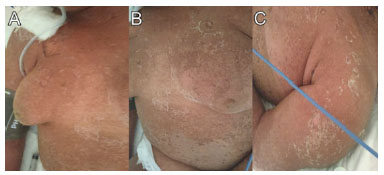

Routine tests were normal. The chest radiograph showed a discrete bilateral interstitial-alveolar infiltrate with a predominance of bases (Figure 6).